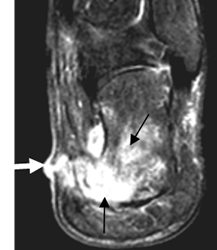

Fig 37. Osteomielitis del calcáneo.

RM coronal en STIR. Osteolisis del calcáneo, con cambios inflamatorios en los tejidos blandos. (Flechas negras). Se identifica trayecto de fístula hiperintensa, hacia la parte interna del pie. (Flecha gruesa).